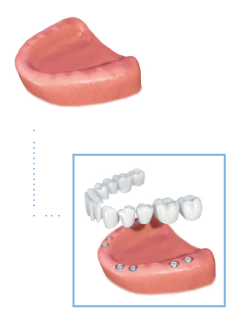

Full arch

As an alternative to a denture it is possible to replace all the teeth in an arch, anchored by several implants. The number of implants required is dependent on the clinical assessment of each individual case.

Dentures

A loose fitting denture is a common problem for thousands of people. Securing dentures using dental implants restores chewing function and reduces irritation of the gums, leading to an enhanced quality of life. The additional support and stability gives the wearer confidence to eat what they want and smile and laugh without being self-conscious.